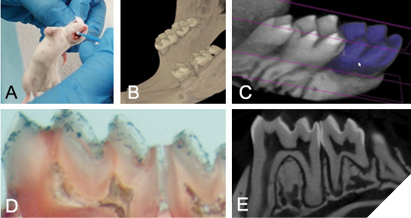

Our in vitro data gives substantial support for commercializing these probiotic products as preventive oral health products for use in humans. Currently, we are actively engaged in planning and/or conducting activities that will move our products into the market. For example, we are planning a series of pre-clinical studies on mice, a powerful way to test the efficacy and safety of therapeutics before translating to humans. Fortunately, in dental research, there exists a well-established rodent model of caries where the formation of caries is induced in rodents by exposing the animals to a high sugar diet combined with inoculation of S. mutans.31 We plan to take advantage of this model and combine our studies with the powerful and highly sensitive micro-computed tomographic technique to generate ultrahigh-resolution images of rodent teeth to determine the impact of our probiotic administration on tooth cavitation (Fig. 5). Another immediate goal of our research is to develop innovative probiotic products that can be readily incorporated into current oral healthcare and treatment modalities for use in the oral cavity. For example, we are actively working with bioengineers and industrial partners to develop delivery formats including powder forms, tablets, and microcapsules (Fig. 6). We are also actively involved in conducting manufacturing, stability and efficacy testing of our finished products, conducting clinical trials to validate claims and safety, obtaining federal regulatory approval for human use, etc.

Fig. 5